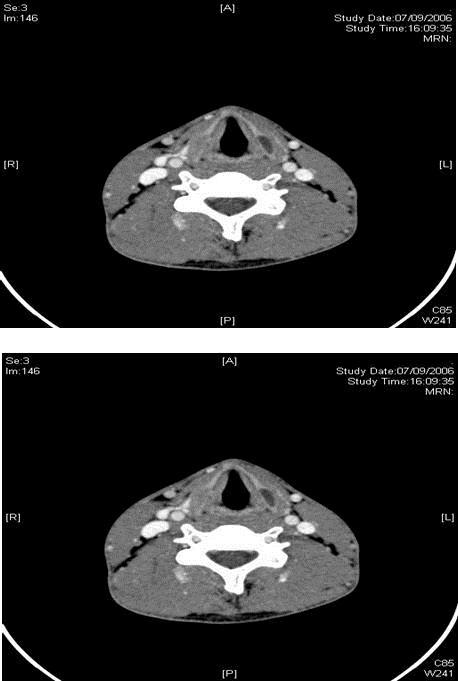

Figure 1.CT scan showing bilateral lamella expansions of the thyroid cartilage with cystic changes on the left

We report a case of a 19 year old gentleman with no significant past medical or family history of note, who first presented with right-sided headache of 1 month duration. CT scan showed focal bony thickening involving the right squamous temporal bone and greater wing of the sphenoid with internal ground-glass appearance, consistent with focal fibrous dysplasia. He re-presented 5 months later with right-sided cervical lymphadenopathy of 1-month duration. Fine needle aspiration cytology showed necrosis with mild acute inflammation. CT scan revealed right-sided suppurative cervical lymph nodes at levels 2 and 3, with an incidental finding of bilateral lamella expansions of the thyroid cartilage with cystic changes on the left, consistent with fibrous dysplasia. Cultures from the aspirate were positive for mycobacterium tuberculosis and the patient was treated with 6 months of anti-tuberculous chemotherapy. He has been followed-up for a 3 year duration, and has since remained well, with no further complaints of headache, neck pain or swelling.